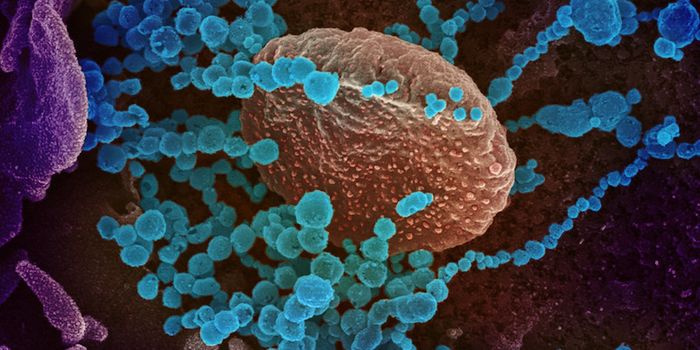

SEP 28, 2020Genetics & GenomicsSince the start of the pandemic, scientists have been trying to find out why some people get such severe illness from SA ...

MAY 03, 2020Genetics & GenomicsThe origin of SARS-CoV-2, the pandemic virus that causes COVID-19, has become politicized as leaders seek to place blame ...

APR 06, 2020Genetics & GenomicsSARS-CoV-2 is the name for the pandemic coronavirus that causes the illness COVID-19, which affects people in extremely ...